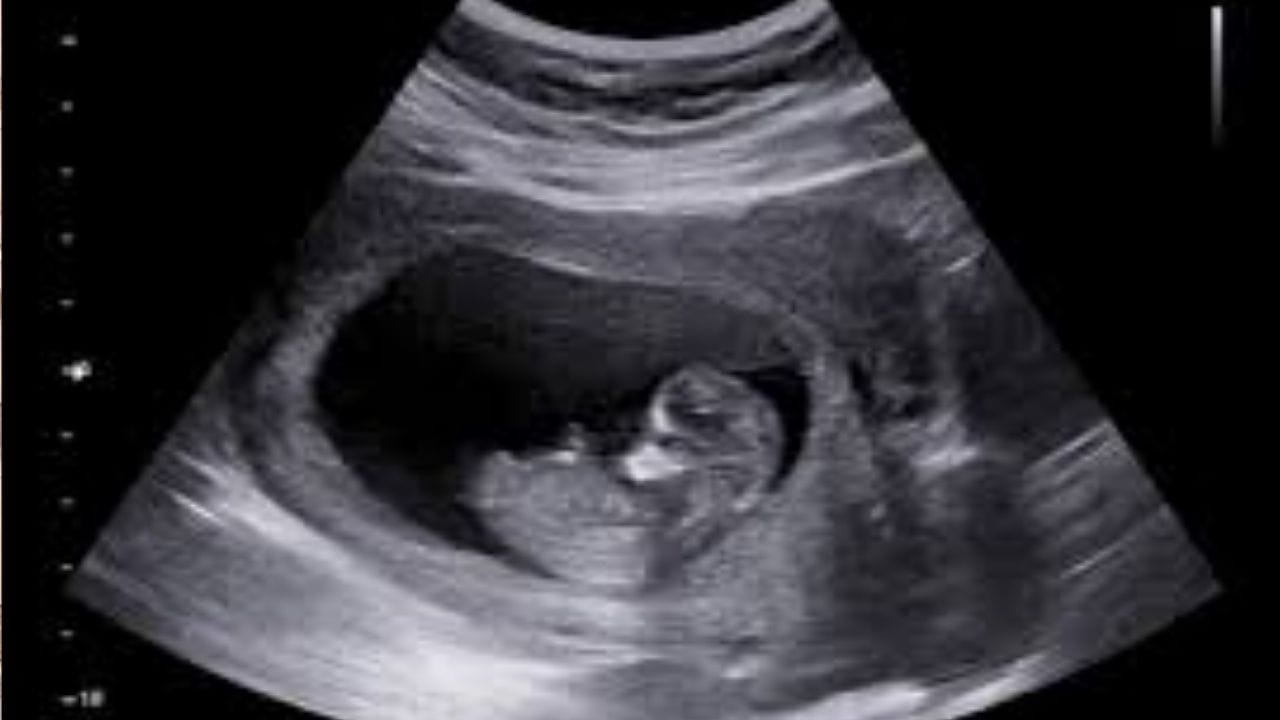

சிசுவின் பாலினத்தை கண்டறிதால் கடும் நடவடிக்கை.. சுகாதாரத்துறை எச்சரிக்கை..

சென்னையில் கருவின் பாலின தேர்வை தடை செய்தல் சட்டத்தின்படி, அமைக்கப்பட்ட மாநில மேற்பார்வை குழு கூட்டம் அண்மையில் நடைபெற்றது. இந்த கூட்டத்தில், பேசிய மக்கள் நல்வாழ்வுத்துறை அமைச்சர் மா. சு. சுப்பிரமணியன் கூறுகையில், தமிழகத்தில் கருவுறுதலுக்கு முன் பாலின தேர்வை தடை செய்யும் சட்டத்தின் அடிப்படையில்